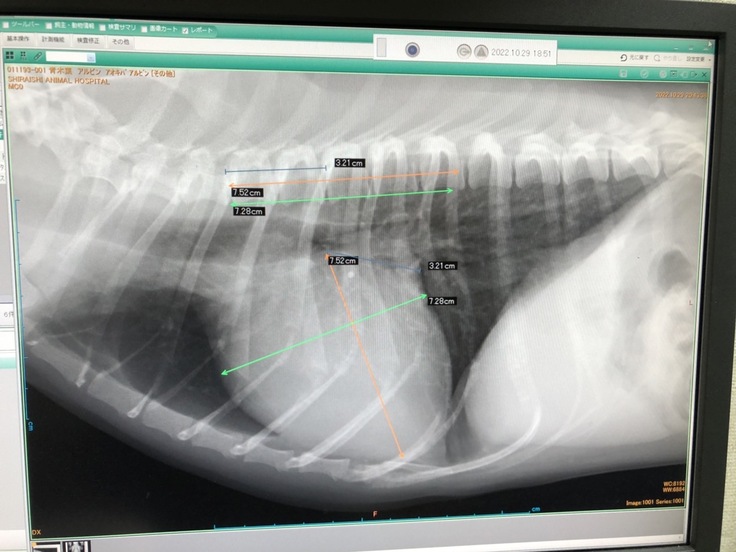

咳のような、くしゃみのような症状が気になり動物病院に行ったところ、心雑音があるとのことでエコー検査を受け心肥大が分かりました。

この手術が出来る病院を調べ受診したところ、「僧帽弁閉鎖不全症」ステージB2 と診断されました。

投薬では進行を遅らせるだけで根治はできないこと、病状が進めば肺に水が溜まり、陸にいながら溺れているように息がしにくくなる肺水腫になってしまう、とありました。